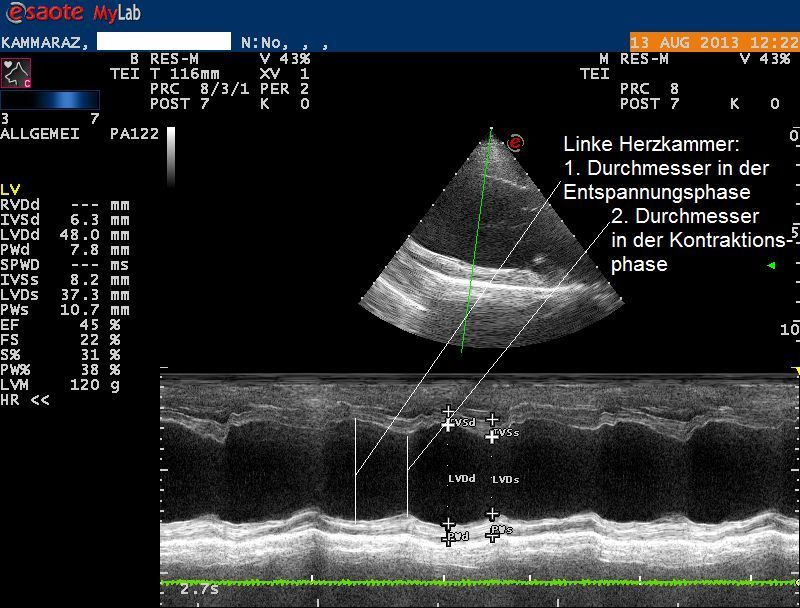

Weiterer Untersuch: Herzultraschall

Der Herzultraschall bestätigt den röntgenologischen Verdacht eines Herzproblems: Sowohl die Hauptkammer als auch der linke Vorhof sind bei Karammaz stark erweitert; die Kammer zieht sich ausserdem in der Pumpphase des Herzen zu wenig zusammen, wodurch das Organ zuwenig Blut fördern kann. Im Doppler-Ultraschall ist zu erkennen, dass durch die Erweiterung des Herzen auch die Klappen zwischen linkem Vorhof und linker Kammer undicht geworden sind und Blut beim Pumpen zum Teil nicht in den Körper, sondern zurück in den Vorhof gepumpt wird. Sonografisch ist also ein typisches Bild einer sogenannten Dilatativen Cardiomyopathie (DCM, Herzmuskelerkrankung, welche mit einer Erweiterung einhergeht) vorhanden; als Folge der geringen Pumpleistung des Herzen hat sich ausserdem ein Lungenödem gebildet.